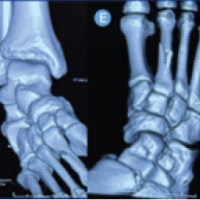

Distal vascular examination showed palpable posterior and anterior tibial pulses. Sensory and motor function of the toes were preserved. Standard anteroposterior and lateral radiographs of the ankle demonstrated a medial peritalar dislocation (Fig. 2).

Figure 2: Preoperative radiographs of the right foot. (a) Standard anteroposterior and (b) lateral radiographs demonstrating isolated medial peritalar dislocation without associated fractures.